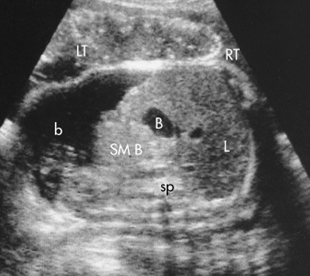

hydronephrosis